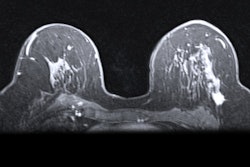

Due to its sensitivity for the detection of small and early infarcts, DWI-MRI is commonly used for evaluation of acute ischemic stroke, according to Hwang. ADC maps can also be used as a reference for acute infarction.

Seeking to develop a deep learning-based automated infarct segmentation model, the researchers first gathered DWI and ADC maps from 394 patients with an acute infarct treated at their institution between January 2015 and May 2019. Of these datasets, 216 were used for training and 24 were utilized for validation. The remaining 154 datasets were set aside for testing of the model.

The team elected to utilize a modified U-Net convolutional neural network in an ensemble approach in order to improve performance on small lesions, according to Hwang. After segmenting the infarct, the algorithm then measures infarct severity based on analysis of the ADC maps of the lesions.

Infarcts are thereby classified into one of four categories: no stroke symptoms, minor stroke, moderate stroke, and severe stroke. An ADC value of more than 620 was used as the threshold for the "no stroke symptoms" category; other category thresholds were set at intervals of 100 ADC values.